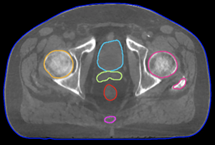

A Harmony a ring lineáris gyorsítók kategóriájában a legjobb multi-leaf kollimatorral (MLC) rendelkező gyorsító. 160 MLC-ből álló, 1 mm-es felbontással a 40 x 40 cm-es mező teljes felületén.